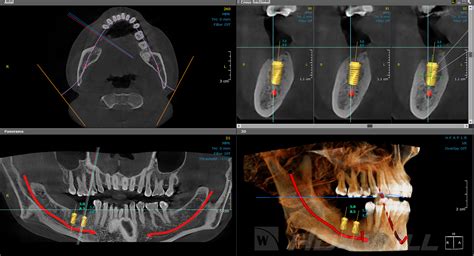

- Colocación de implantes: El TAC es imprescindible antes de la colocación de implantes dentales. Se usa durante la fase de estudio para observar y analizar las estructuras óseas del paciente.

Hoy en día, la inmensa mayoría de los TAC dentales que utilizamos son digitales. Desde el monitor, el odontólogo podrá estudiar en detalle la imagen final para establecer el diagnóstico del paciente y determinar el tratamiento a seguir.

- Implantología: Permite establecer una evaluación preoperatoria del diagnóstico tras un examen clínico y radiológico estándar del paciente, para establecer la conveniencia de la colocación del implante en caso de duda o establecer la contraindicación, y en algunos casos para realizar el seguimiento postoperatorio.

Con el TAC mandibular y maxilar podemos medir la anchura, altura y espacio disponible para insertar los implantes. Estudiar las estructuras óseas es esencial para determinar la posición exacta del tornillo, además de asegurar el éxito de la cirugía. La planificación de la cirugía guiada por ordenador combinada con la carga inmediata permite recuperar todos los dientes en un día.